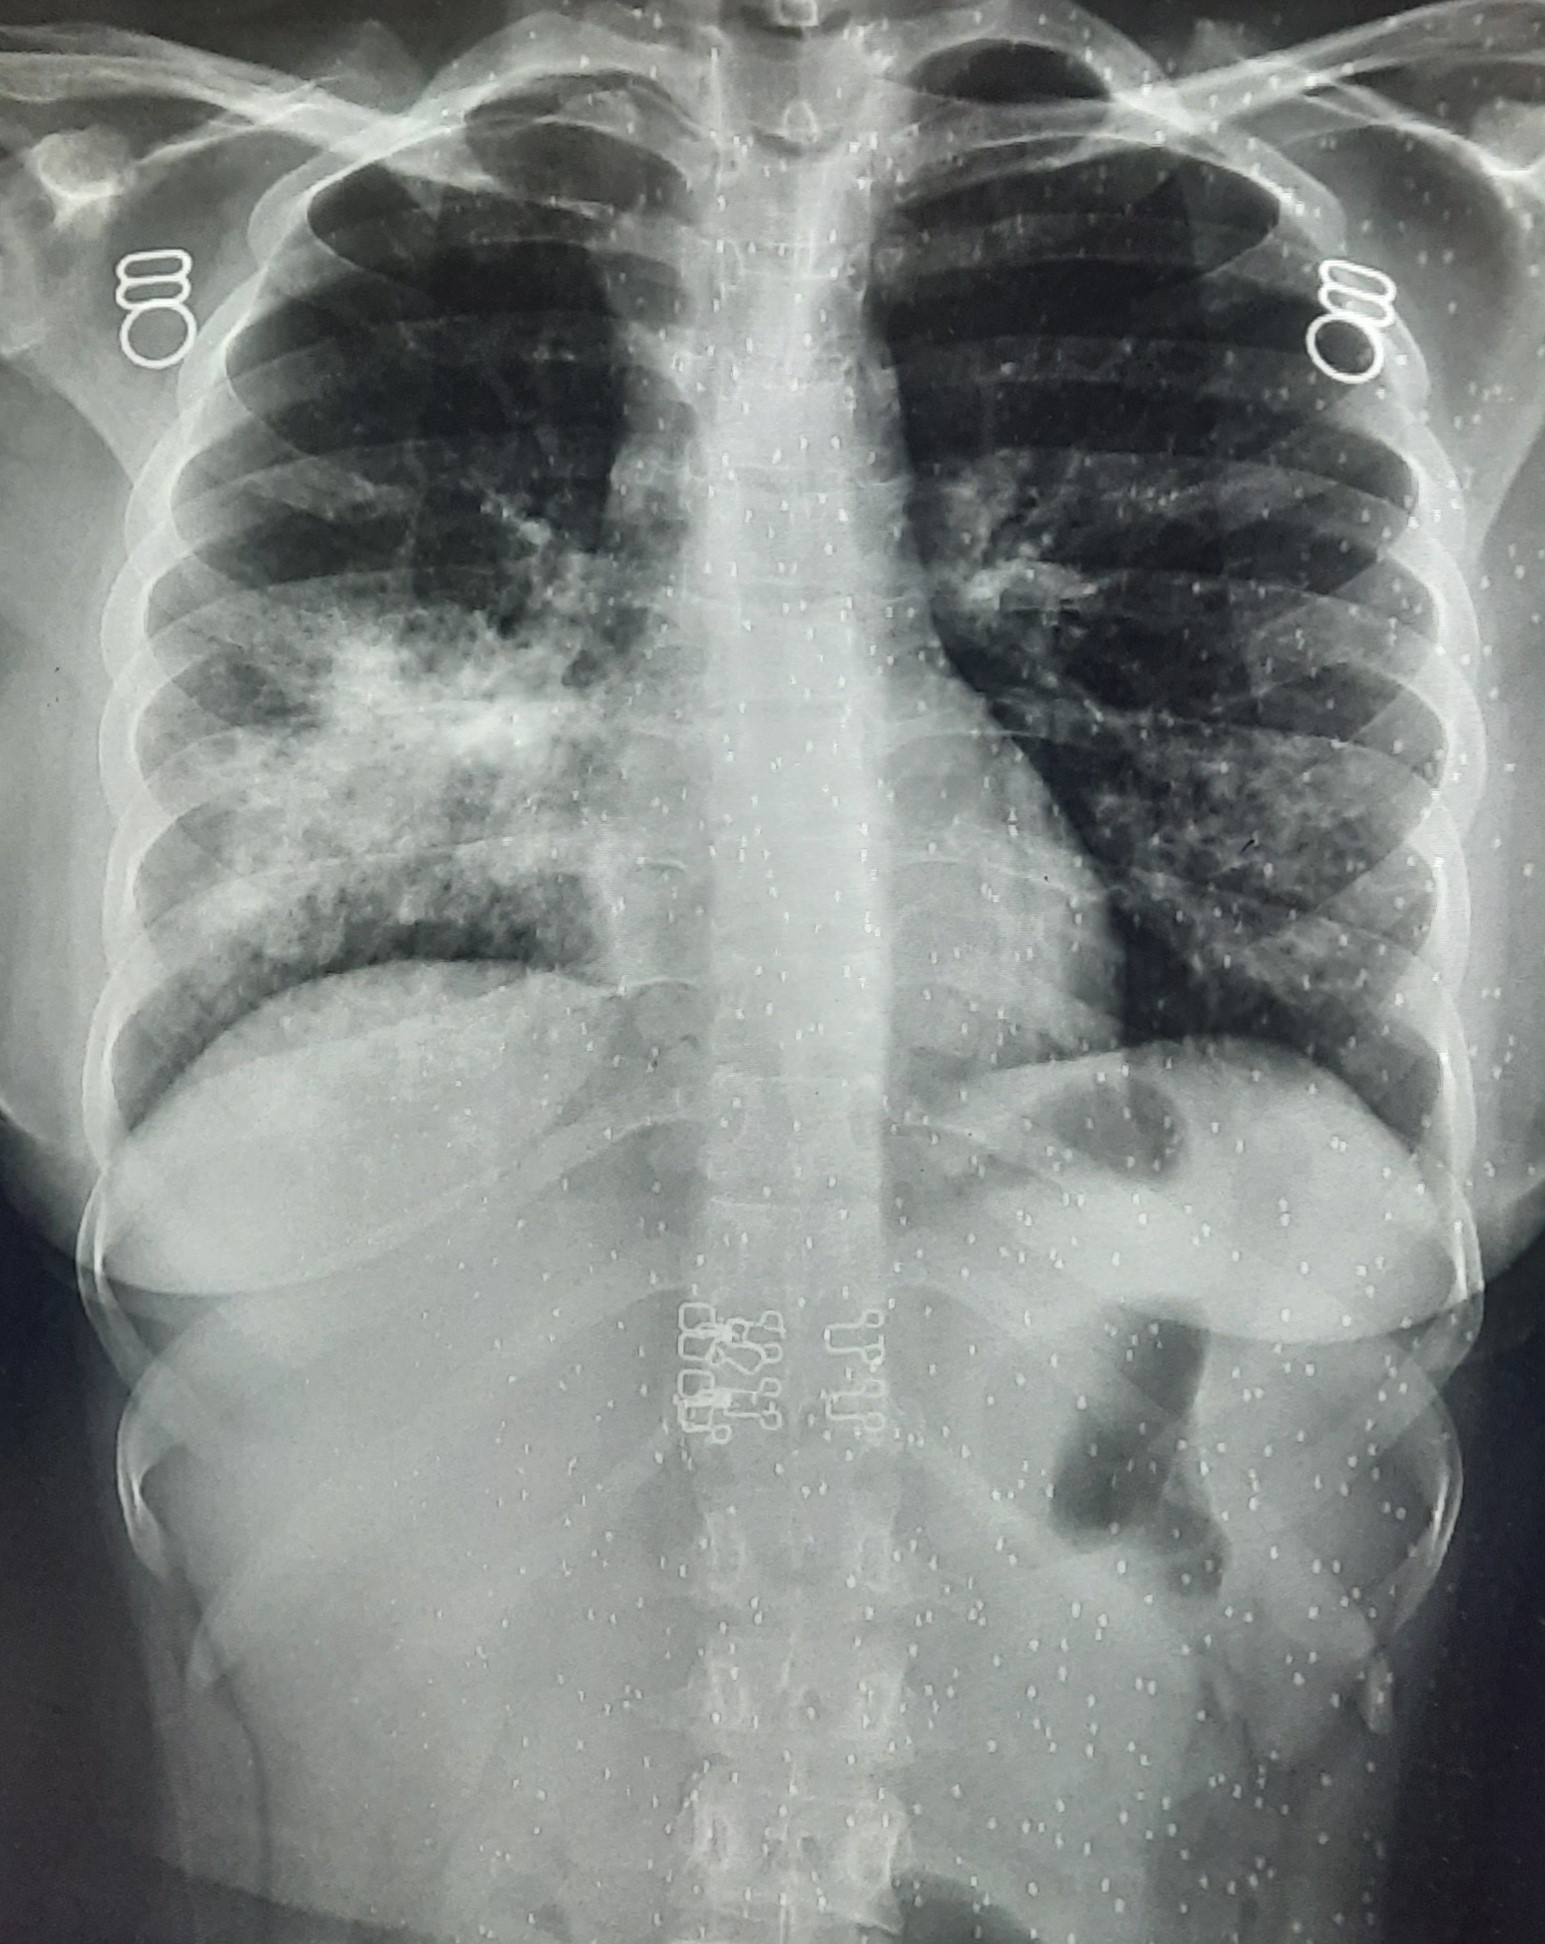

| 251 | IGGMC, Nagpur, Nagpur | P2 | 29-4221 | Ganpat Gaikawad | Consent taken on Paper | 70 Yrs. |

Provisional Diag : post TB sequele?

Final Diag : Fibrosis |

Non-TB Case (Confirmed) | Fibrosis | Abnormality visible on x-ray |